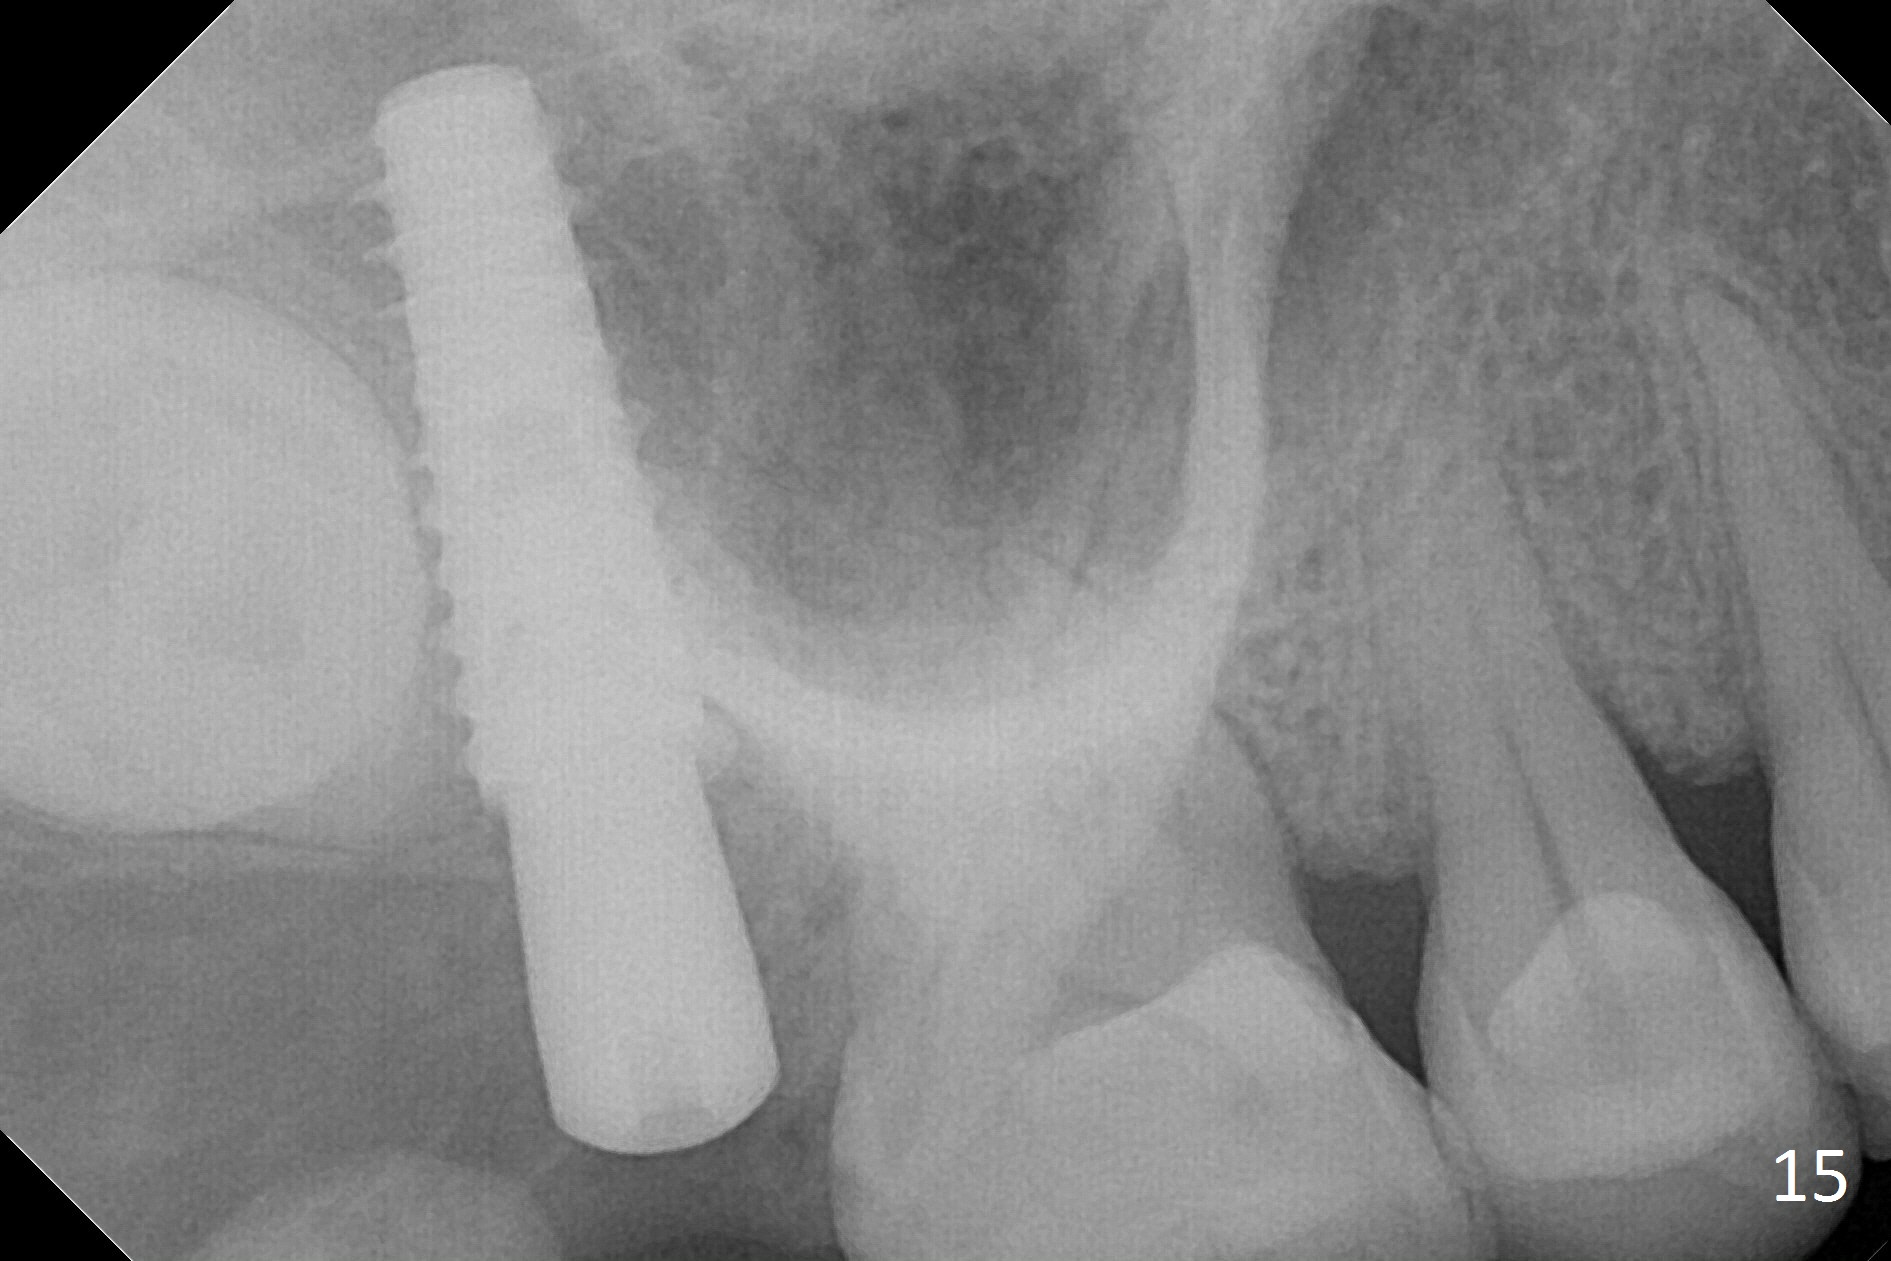

In fact, the implant is reversely torqued (1 month postop) and ~ 2 mm more coronally. It becomes looser. A healing screw is placed. With insertion of collagen plug, sutures are placed. Five days postop, the wound appears to be healing with sutures being dissolved. Four months later (5 months post placement), the patient returns asymptomatic. The wound heals. The implant appears to have osteointegrated and is at the crestal level (Fig.13,14). At uncover, the implant is found unstable; a healing abutment is placed. The implant is stable 8 months postop with apparently no gap between the bone and threads (Fig.15, as compared to Fig.13).